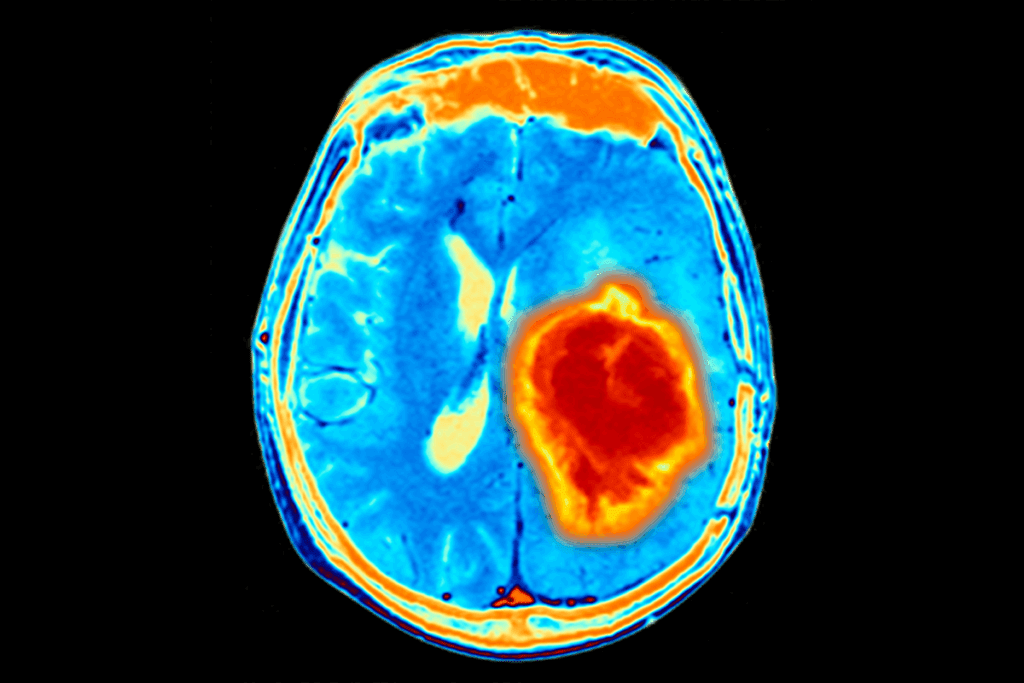

Solid tumors are different from liquid tumors like leukemias, which affect the blood. Solid tumors form a mass that can be seen with imaging like X-rays or CT scans.

- Imaging Tests: CT scans, MRI, and PET scans show the tumor’s size, location, and spread.